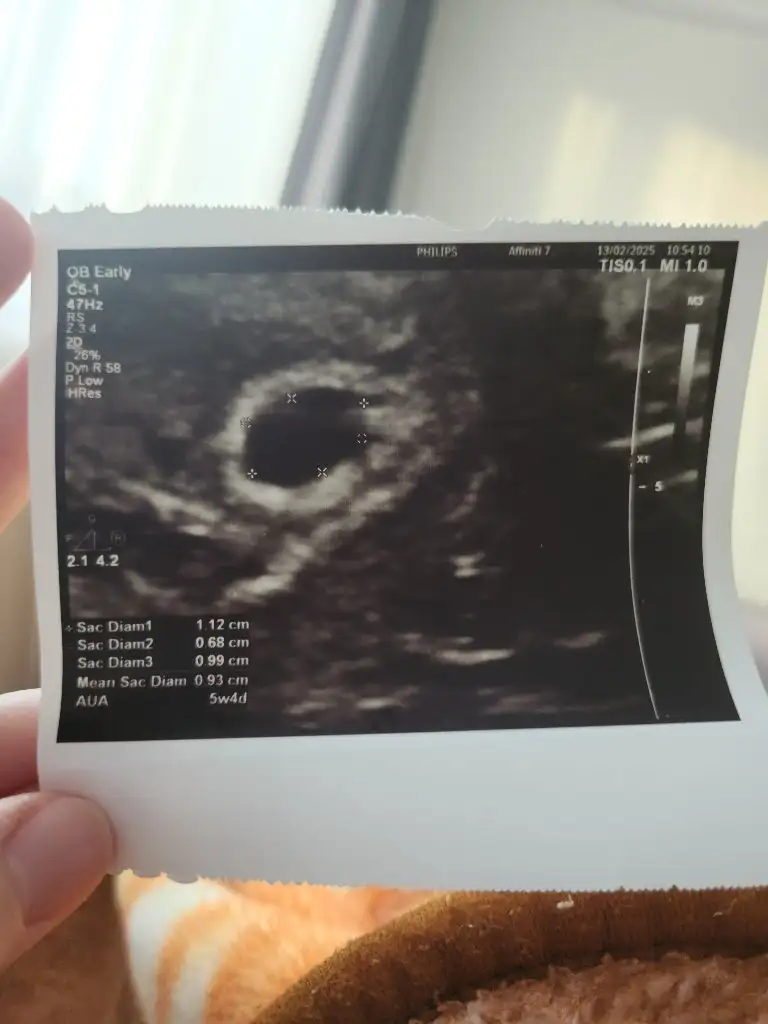

Kese boyu falan bişe demedi demiyo mu acaba ilk olunca heyecandan hiç bişe sormadım canım ya 5 hafta 4 gün dedi de başka bişe sormak aklıma gelmedi kafam gitmişti

Kese boyutu 1.12 cm çıkmış en büyük ölçü

5 hafta 4 günlük yazıyor birde

Normal yani 😊 ne sormak istedin başka